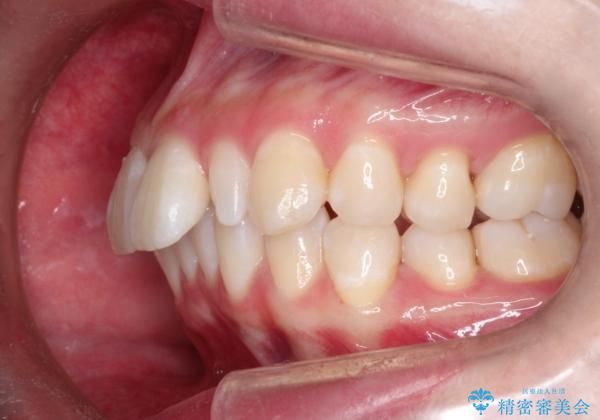

- 出っ歯と全体をきれいにしたいとのことで来院されました。

上顎の歯が全体的に前方に位置しているのと、前から2番目の歯が通常よりも小さい矮小歯という状態でした。

出っ歯をなおすために上顎の前から4番目の歯を抜歯して、引っ込めるのと、前から2番目の歯に通常の大きさのオールセラミックを装着して整った歯並びにすることにしました。